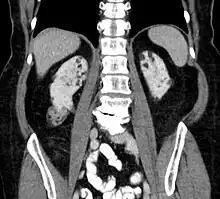

Kidneys

Between 26% and 80% of TSC patients have benign tumors of the kidneys called angiomyolipomas, with hematuria being the most frequent presenting symptom. [9] TSC angiomyolipomas differ from non-TSC angiomyolipomas in age of presentation (31.5 years vs 53.6 years), mean tumor size (8.2 cm vs 4.5 cm), and percentage of cases requiring surgical intervention (50% vs 28%).[9] Although benign, an angiomyolipoma larger than 4 cm is at risk for a potentially catastrophic hemorrhage, either spontaneously or with minimal trauma.

- Repeat MRI of abdomen every one to three years throughout life. Check renal (kidney) function annually. Should angiomyolipoma bleed, this is best treated with embolisation and then corticosteroids. Removal of the kidney (nephrectomy) is strongly to be avoided. An asymptomatic angiomyolipoma that is growing larger than 3 cm is best treated with an mTOR inhibitor drug. Other renal complications spotted by imaging include polycystic kidney disease and renal cell carcinoma.